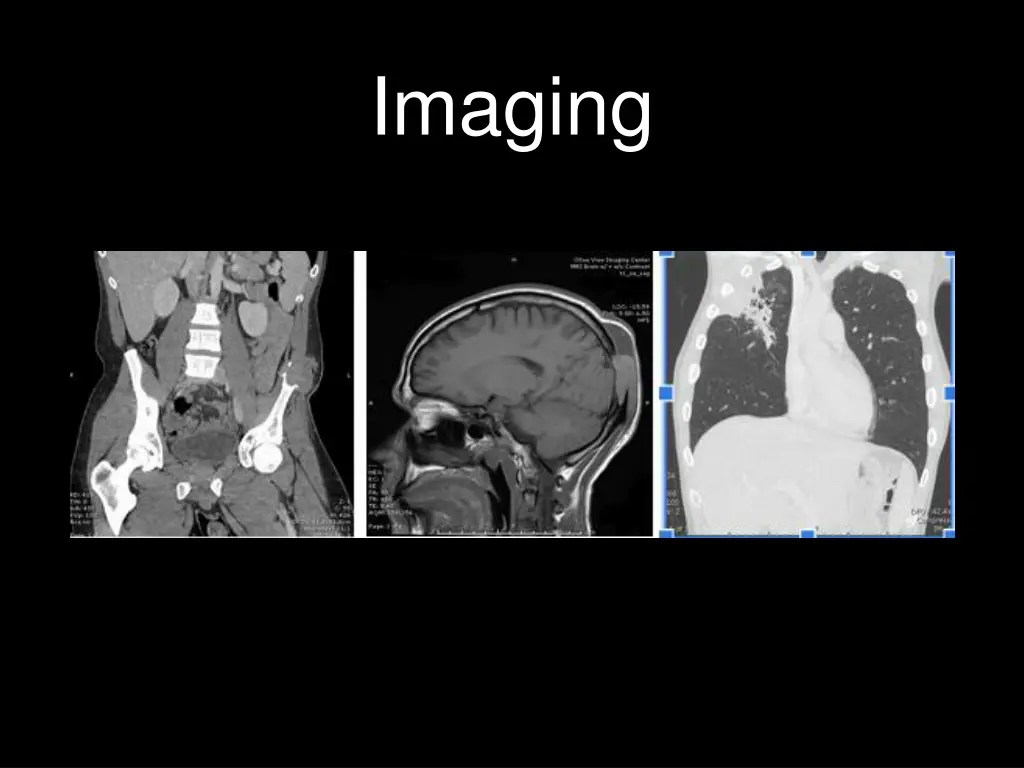

Hospital Course Given the subacute involvement of multiple organs, a disseminated atypical infectious process was suspected early with Blastomyces of concern given the patient s origin. Skin punch biopsy of the right wrist staining with GMS and PAS-D revealed spherical double-contoured fungal yeast with broad based buds in multinucleated giant cells, with dermal granulomatous inflammation and micro-abscesses consistent with blastomycosis. The patient was started on liposomal amphotericin within 72 hours of presentation given concern for CNS involvement. Fungal cultures from both the draining flank abscess and right wrist skin biopsy grew Blastomycosis dermatitidis identified via DNA probe on day 17 confirming the diagnosis of disseminated blastomycosis.